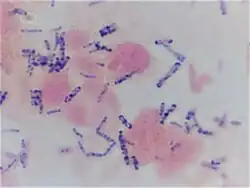

All wounds are considered to harbor microorganisms. Management of the bacterial balance is of vital importance if delays in healing are to be avoided. The biological removal of micro-organisms, including potential pathogens, and tissue debris from the wound of an immune-competent patient is a wound cleansing activity that takes place almost immediately after wounding and which helps to reduce the threat of infection. However, a range of risk factors exist that increase the likelihood of infection intervening, and these include; age, depleted nutrition, down-regulation of the immune system, systemic disease, and poor tissue perfusion of oxygen. Thus, in the above circumstances or when a wound has become infected, wound cleansing activities beyond the natural biological processes are required so that the wound bioburden is maintained at a level where the host can remain in control.

Attaching to a surface is a natural association for bacteria in the wild. Biofilm phenotype bacteria are microbial communities that are attached to a surface and are embedded in an extracellular polymeric substance (EPS) consisting of proteins, glycoproteins, nucleic acids (RNA, DNA) and polysaccharides (slime).[12] This mantle affords protection from antimicrobial and cellular attack. In contrast, planktonic phenotype bacteria are free-floating in nature and do not possess the defence structures afforded by the creation of the EPS slime. Within the biofilm, a rich biological diversity may be found. The attached (sessile) bacteria release proteases which help to perpetuate a chronic inflammatory state.[13] Therefore, the potential exists for these exogenous proteases to work in tandem with endogenously produced proteases and degrade growth factors and tissue proteins that are necessary for the healing process.

We are developing greater insight into the association between delayed healing and the presence of biofilm.[14][15] The relationship between delayed healing and the need for debridement is also being acknowledged.[16] It has been suggested that the presence of wound slough provides an indication of biofilm presence,[17] therefore, indicating the need to reduce the wound bioburden.

In vitro studies on clinical isolates of E. coli and S. epidermidis have demonstrated the anti-biofilm efficacy of PHMB. The activity of five biocides at various concentrations was recorded following exposure to the isolates. The biocides found to be most active towards planktonic (free floating) cells were PHMB and peracetic acid. A corresponding level of activity towards biofilm phenotype bacteria was also found with the two agents.[34][35]